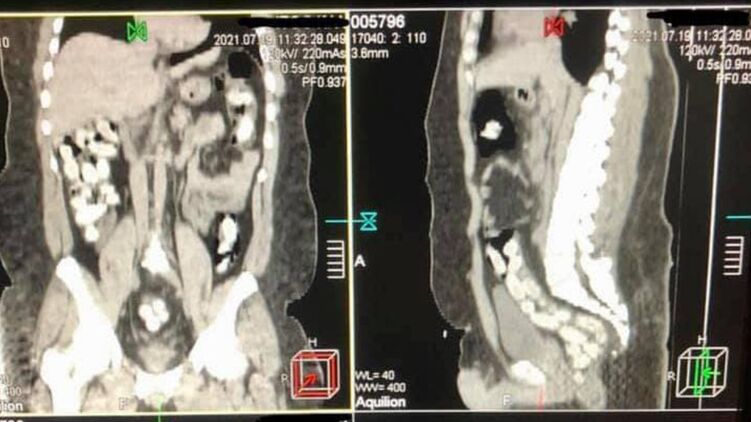

"В июле 2021 года в Борисполе был задержан бразилец, который в желудке ввез в Украину почти 1 кг кокаина. Мужчина проглотил 90 капсул, которые извлекали из кишечника медикаментозным путем после компьютерной томографии", - говорится в сообщении.

Напомним, 29-летний курьер с начиненными кокаином капсулами в желудке прибыл в аэропорт "Борисполь". Имея предварительную оперативную информацию, таможенники применили в отношении иностранца личный досмотр с привлечением медицинского работника. Процедура проходила в медицинском учреждении с применением компьютерной томографии брюшной полости мужчины.

Изъятие 90 капсул овальной формы, которые находились в его кишечнике, происходило медикаментозным путем и длилось почти три часа.